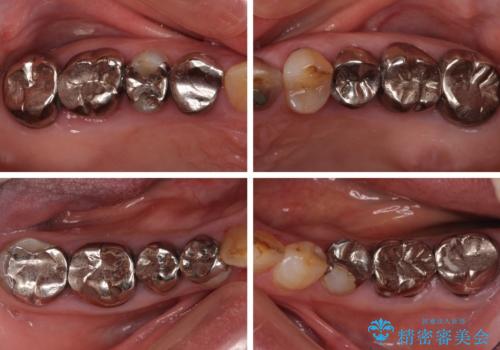

全ての奥歯の銀歯をセラミックに メタルフリー治療

- 奥歯に装着されている銀歯を全て外したいとのことで来院された患者様です。

土台に含まれている金属も含め、奥歯の金属は全て除去し、オールセラミッククラウンやセラミックインレーにて治療することとしました。